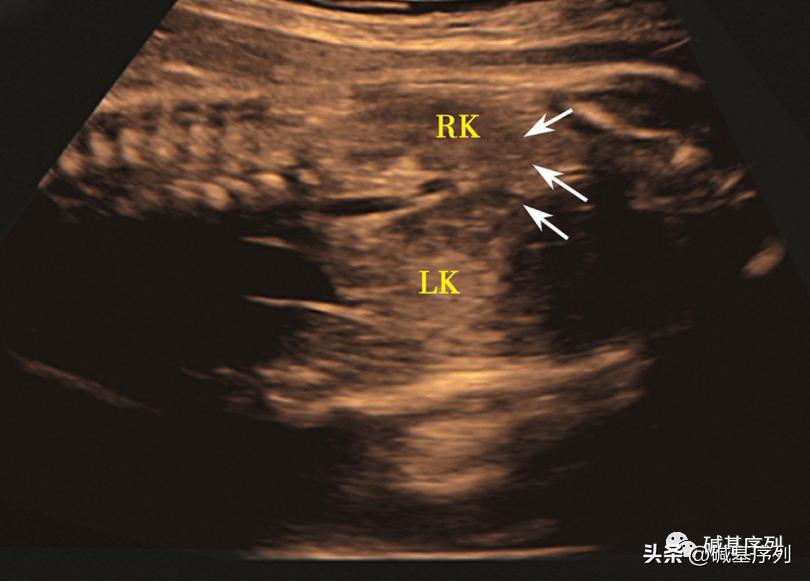

横跨中线连接两侧肾脏下极的区域为马蹄肾的峡部,在超声成像中通过峡部区域获取肾脏的横断切面或冠状切面能很好地诊断出马蹄肾。

马蹄肾超声图示:孕28周,胎儿腹部冠状切面,可见双侧肾脏下极融合位于脊柱前面膀胱上方,呈“U”形(箭头所指)